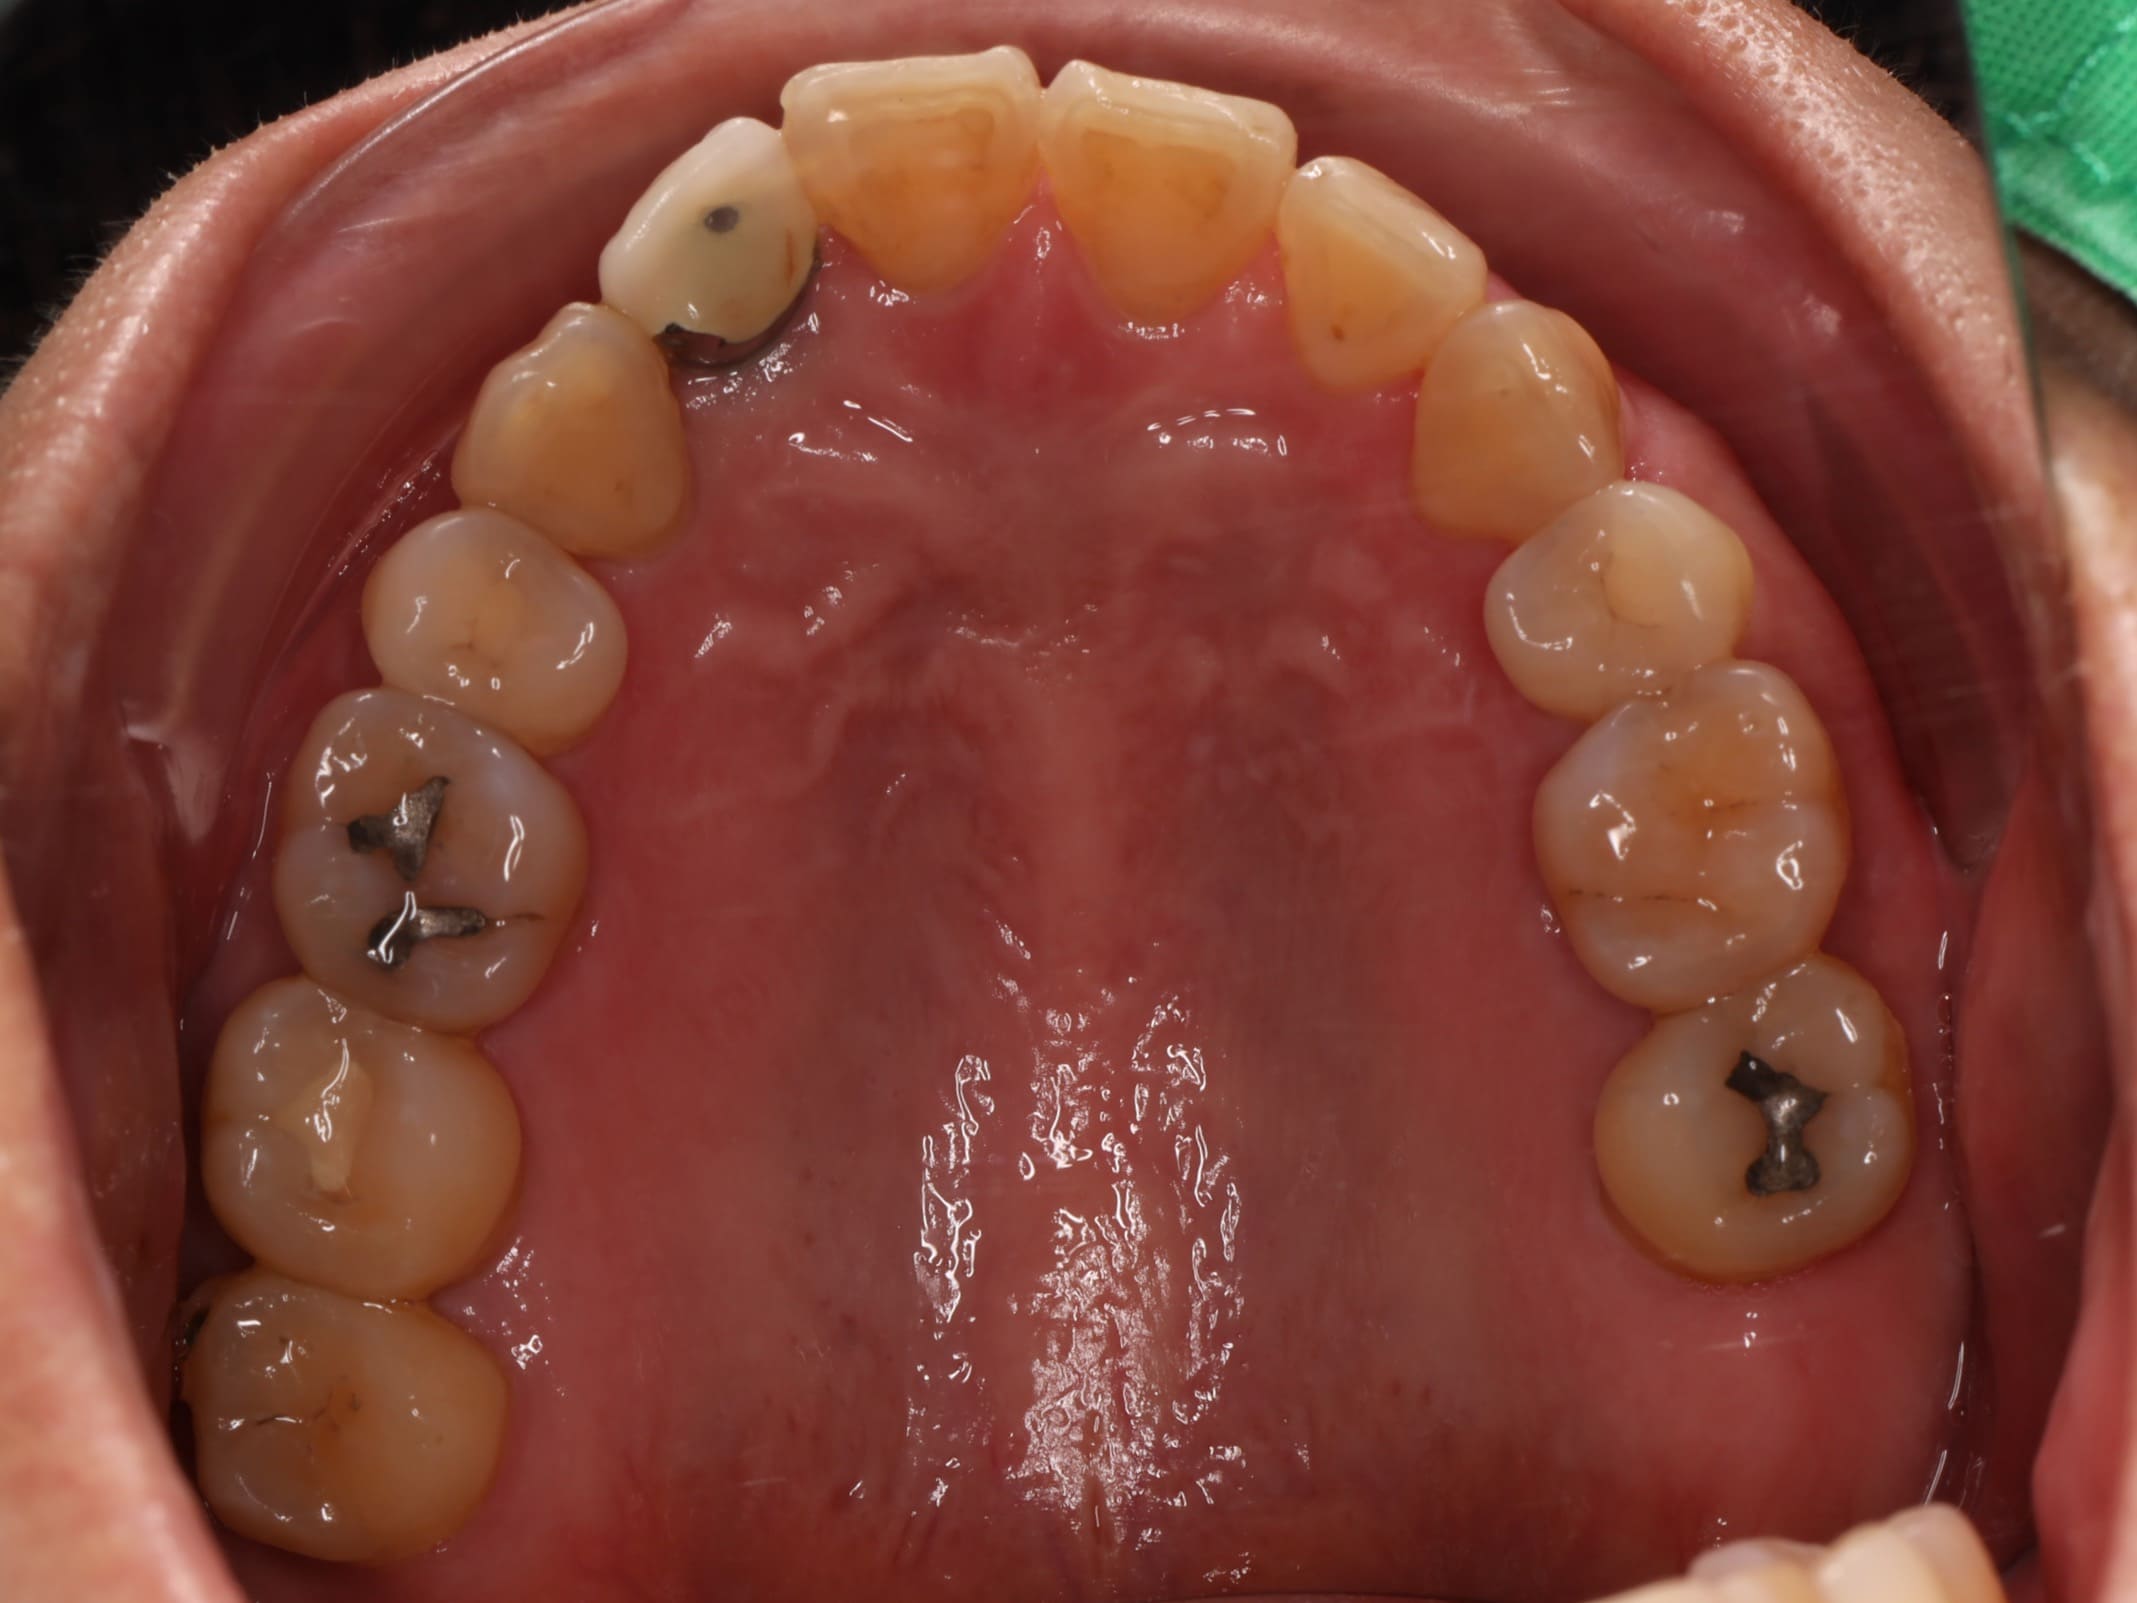

首先是 牙齒排列不整,她年輕時曾接受過矯正治療,但因為沒有持續佩戴維持器,導致牙齒在不知不覺間位移,不僅影響外觀,也讓日常清潔變得困難。再來是 牙周病問題,雖然患者有在其他診所進行治療,但由於右下側有一顆牙齒搖晃得非常厲害,牙周破壞的情況相當嚴重,原本的醫師告知她可能無法保留。最後是 舊假牙美觀不佳 的問題,患者的右上側門牙曾做過植牙治療,但牙套的角度讓牙齒看起來有些傾斜,並非正對前方,視覺上顯得不協調。此外,口內還有一些早期製作的舊牙套,邊緣都露出黑黑的金屬邊,每次張嘴說話都感到不自在。